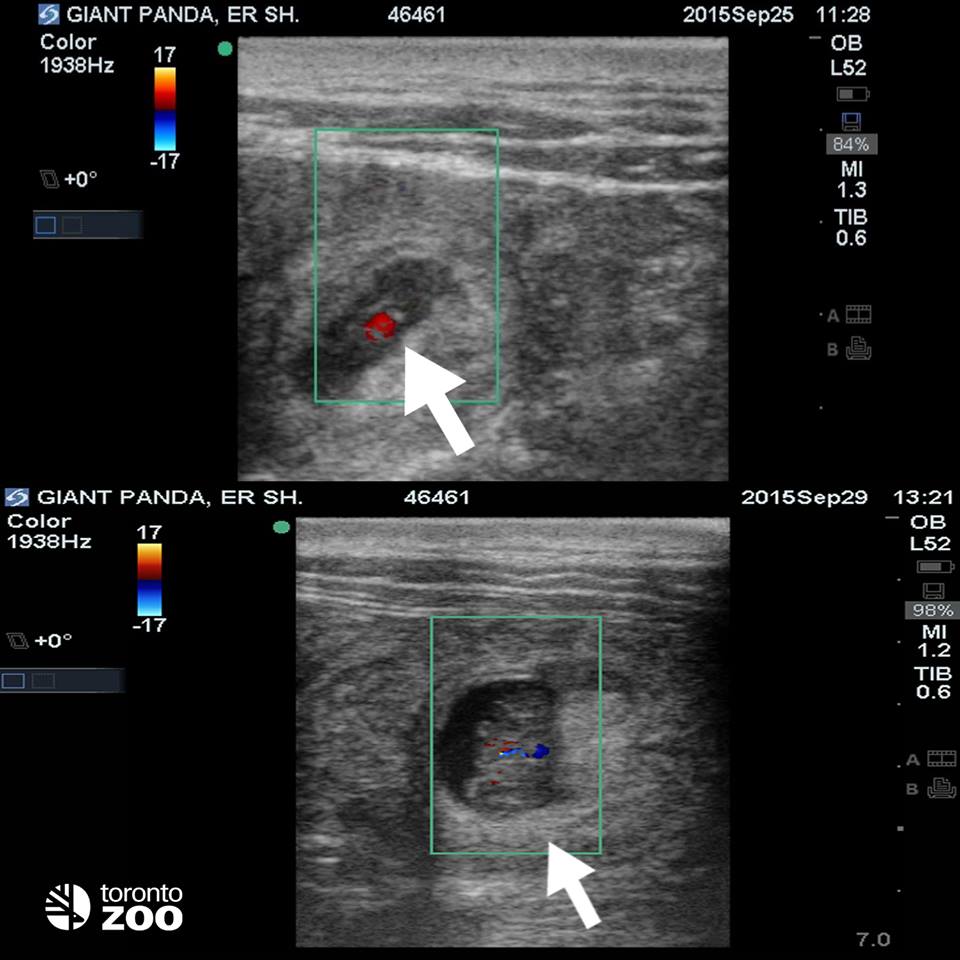

On Sept. 25, a fetal heartbeat was seen on ultrasound. Then, another ultrasound on Sept. 29 detected a second fetus.